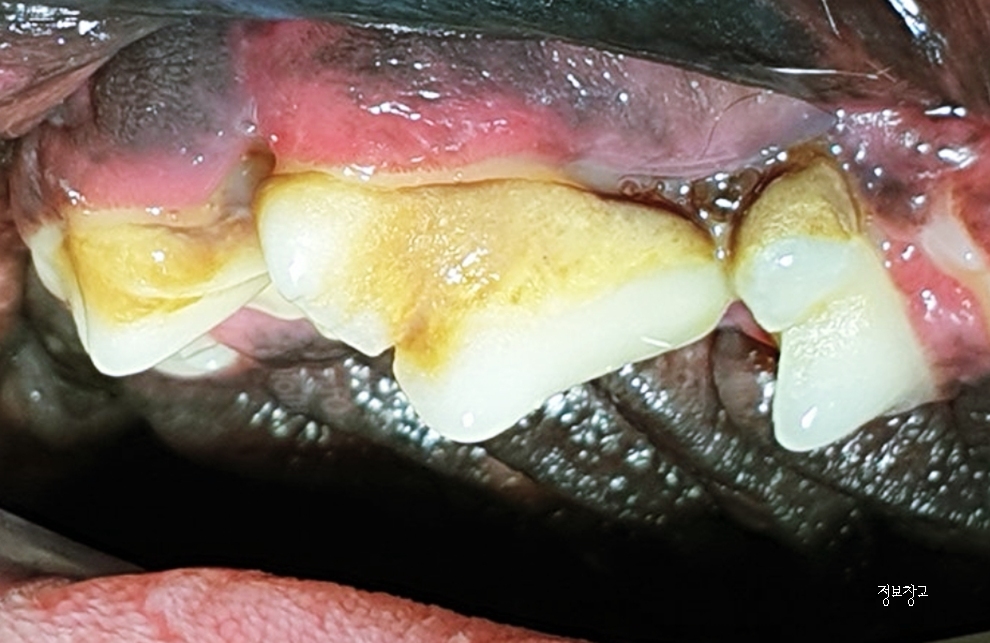

① 치석·치태 축적 (가장 흔한 원인)

강아지 입냄새의 가장 큰 원인입니다.

특징

- 노란색·갈색 치석이 치아에 붙어 있음

- 잇몸이 붉거나 부어 있음

- 입에서 썩은 냄새

👉 방치 시 치주염 → 치아 손실로 이어질 수 있습니다.